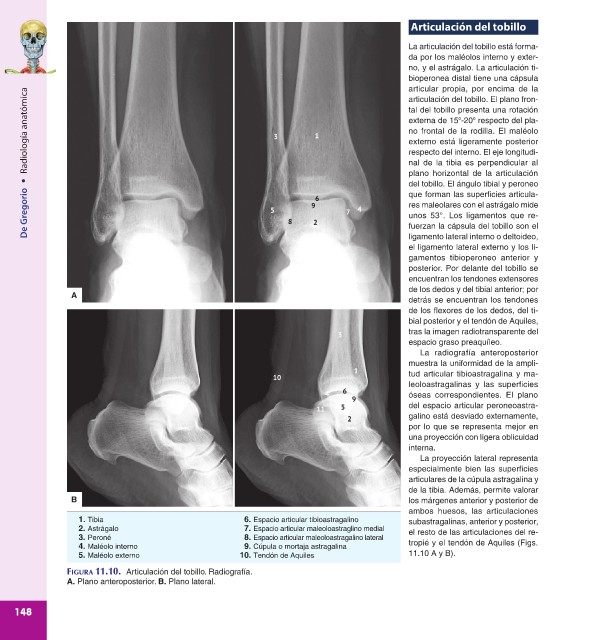

Articulación del tobillo

La articulación del tobillo está forma-

da por los maléolos interno y exter-

no, y el astrágalo. La articulación ti-

bioperonea distal tiene una cápsula

articular propia, por encima de la

Radiología anatómica 3 1 tal del tobillo presenta una rotación

articulación del tobillo. El plano fron-

o

externa de 15 -20 respecto del pla-

no frontal de la rodilla. El maléolo

externo está ligeramente posterior

respecto del interno. El eje longitudi-

plano horizontal de la articulación

• nal de la tibia es perpendicular al

del tobillo. El ángulo tibial y peroneo

De Gregorio 5 8 9 2 6 7 4 res maleolares con el astrágalo mide

que forman las superficies articula-

unos 53°. Los ligamentos que re-

fuerzan la cápsula del tobillo son el

ligamento lateral interno o deltoideo,

el ligamento lateral externo y los li-

gamentos tibioperoneo anterior y

posterior. Por delante del tobillo se

encuentran los tendones extensores

de los dedos y del tibial anterior; por

A

detrás se encuentran los tendones

de los flexores de los dedos, del ti-

bial posterior y el tendón de Aquiles,

3 tras la imagen radiotransparente del

espacio graso preaquíleo.

La radiografía anteroposterior

muestra la uniformidad de la ampli-

10 tud articular tibioastragalina y ma-

leoloastragalinas y las superficies

4 6 óseas correspondientes. El plano

11 5 del espacio articular peroneoastra-

2 galino está desviado externamente,

por lo que se representa mejor en

una proyección con ligera oblicuidad

interna.

La proyección lateral representa

especialmente bien las superficies

articulares de la cúpula astragalina y

de la tibia. Además, permite valorar

B los márgenes anterior y posterior de

ambos huesos, las articulaciones

1. Tibia 6. Espacio articular tibioastragalino subastragalinas, anterior y posterior,

2. Astrágalo 7. Espacio articular maleoloastraglino medial el resto de las articulaciones del re-

3. Peroné 8. Espacio articular maleoloastragalino lateral tropié y el tendón de Aquiles (Figs.

4. Maléolo interno 9. Cúpula o mortaja astragalina

5. Maléolo externo 10. Tendón de Aquiles 11.10 A y B).

FIGURA 11.10. Articulación del tobillo. Radiografía.

A. Plano anteroposterior. B. Plano lateral.